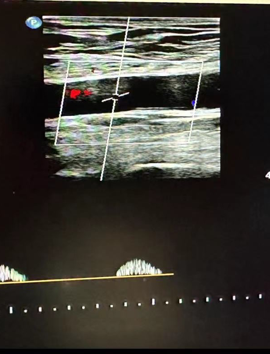

心功能室的李月医生在检查时敏锐捕捉到异常信号:双侧股总动脉血流频谱呈特征性“小慢波”——这通常是大血管严重狭窄的强烈提示。